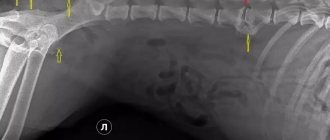

Дискоспондилит у собаки